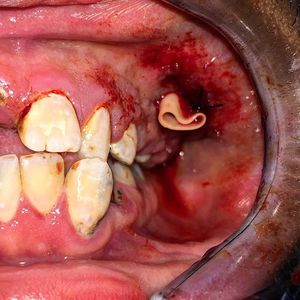

These procedures are often required for infections from decayed teeth This is what happens as a result from neglecting oral hygiene and a lack of professional dental care π¨ββοΈAn incision is made in the vestibule near the offending tooth, the pus is drained and irrigated with saline. The drain is then secured with a silk stitch, allowing the site to continually drain for several days. A course of antibiotics and extracting to tooth is ultimately required for definitive treatment ππ